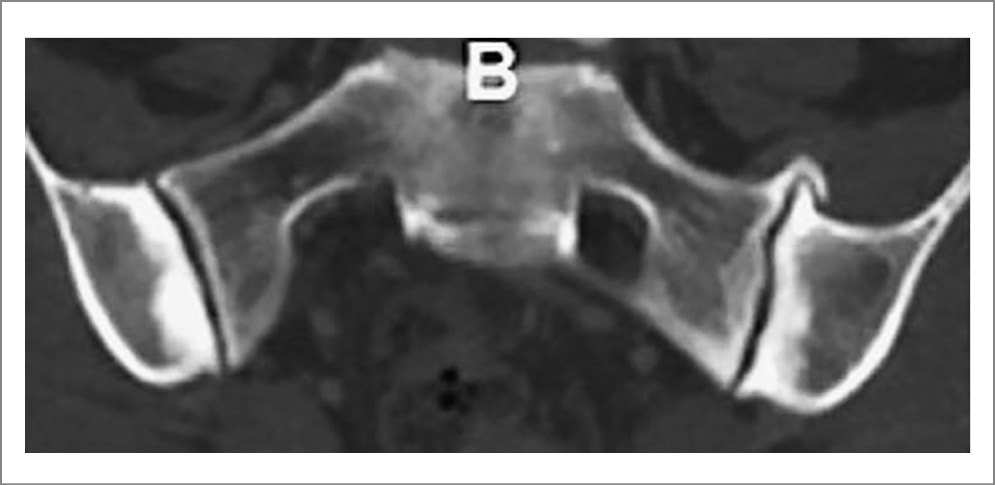

Рис. 4. Пациентка П., диагноз АС, длительность болезни 12 мес: a – КТ крестцово-подвздошных сочленений (коронарная проекция) показала широкий субхондральный склероз подвздошных костей, краевые эрозии подвздошных костей и крестца, расширение суставной щели с обеих сторон (двусторонний определенный сакроилиит); b – на рентгенограмме крестцово-подвздошных сочленений этой же пациентки (сделана незадолго до КТ) изменения (субхондральный склероз, подозрение на расширение щели в средней части левого сустава) видны далеко не так отчетливо, как на КТ.